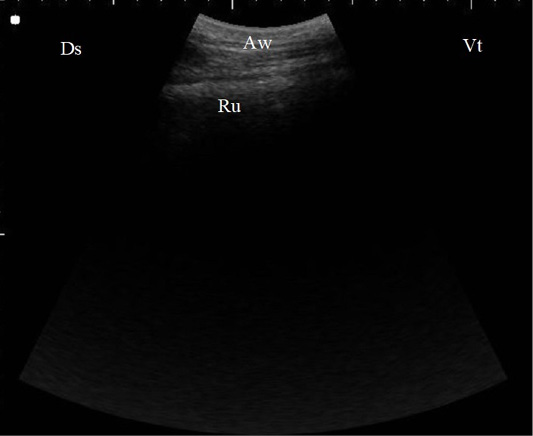

B. Mode ultrasonographic image of the rumen screened from the left flank region in a healthy cow. The ruminal wall (Ru) appeared as an echogenic wall with 0.3 to 0.5 cm in diameter located medial to the abdominal wall (Aw), Ds: Dorsal, Vt: Ventral.